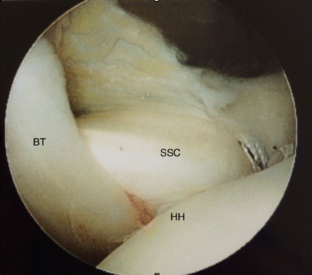

Fig. 2